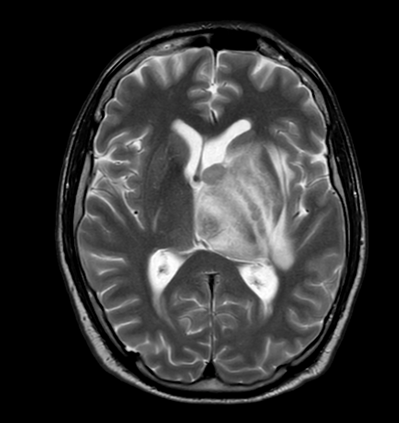

In this study, we aim to initiate the development of Radiology Foundation Model, termed as RadFM.We consider the construction of foundational models from the perspectives of data, model design, and evaluation thoroughly. Our contribution can be concluded as follows: (i), we construct a large-scale Medical Multi-modal Dataset, MedMD, consisting of 16M 2D and 3D medical scans. To the best of our knowledge, this is the first multi-modal dataset containing 3D medical scans. (ii), We propose an architecture that enables visually conditioned generative pre-training, allowing for the integration of text input interleaved with 2D or 3D medical scans to generate response for diverse radiologic tasks. The model was initially pre-trained on MedMD and subsequently domain-specific fine-tuned on RadMD, a radiologic cleaned version of MedMD, containing 3M radiologic visual-language pairs. (iii), we propose a new evaluation benchmark that comprises five tasks, aiming to comprehensively assess the capability of foundation models in handling practical clinical problems. Our experimental results confirm that RadFM significantly outperforms existing multi-modal foundation models. The codes, data, and model checkpoint will all be made publicly available to promote further research and development in the field.